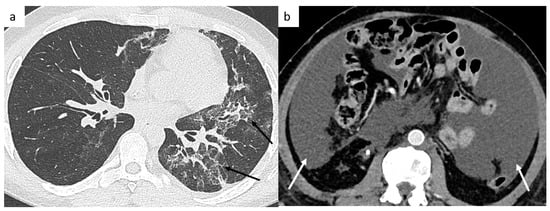

4.5.1. Bleomycin-Induced Pneumonitis

In patients treated with Bleomycin, etoposide and cisplatin (BEP) chemotherapy, bleomycin-induced pulmonary toxicity is a well-known side effect, observed in approximately 10% of patients treated (Figure 8). It can occur during bleomycin treatment leading to treatment discontinuation, or can develop after a free-treatment interval of weeks to months. It can be fatal in 1–3% of affected patients. Risk factors are the cumulative dose of bleomycin, smoking, impaired renal function, older age. The radiological signs are non-specific and consist of a newly developing interstitial pneumonitis since the start of the bleomycin treatment, not explained by infection or previous fibrosis. It can be unifocal, multifocal, uni- or bilateral and can affect several lobes. Most of these radiological changes appear to resolve on follow-up CT scans [65].

Figure 8.

Post-treatment complications. Thoracic CT shows a bleomycin-induced interstitial pneumonitis (a) affecting left upper and lower lobes. Postoperative abdominal CT shows chylous ascites (b).

4.5.2. Post-Surgical Complications

Surgical complications are an ongoing issue in post-chemotherapy retroperitoneal lymph node dissection for surgical resection of residual masses [66]. This surgery is technically much more challenging than primary resections because of desmoplastic reactions as an effect of chemotherapy.

The most frequent complications are lymphatic complications such as lymphatic leakage due to the injury of lymphatic channels during retroperitoneal lymph node dissection, most commonly lymphocele and chylous ascites [67]. Chylous ascites is the accumulation of lymph fluid in the peritoneal cavity (Figure 8). Lymphocele is a cyst filled by lymph fluid, and inflammatory reactions are possible, which can account for a greater size during follow-up. Usually asymptomatic, lymphoceles invariably decrease in size over time after surgery and can resolve completely within a few months without any treatment. A surgical intervention may be required if the lymphocele is symptomatic, infected, or compresses vital structures. Body mass index and the number of resected lymph nodes are well-known factors impacting the incidence of lymphocele.